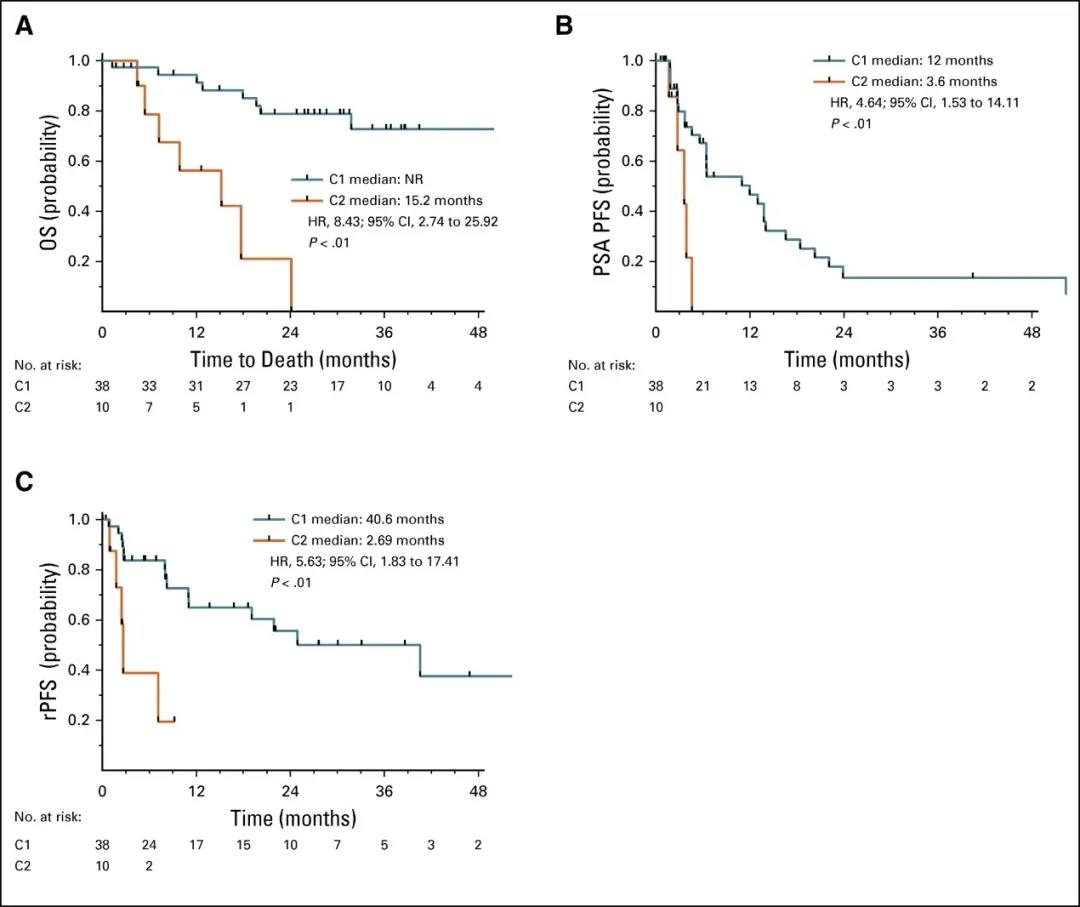

液体活检获得的 CTC 的转录谱结果可作为转移性前列腺癌患者的孤立预后标志物并预测耐药

几乎所有接受雄激素受体(AR)信号抑制剂(ARSI)治疗的前列腺癌男性都会通过多种机制产生耐药性,包括 AR 通路的激活,AR 基因结构改变、AR 剪接变体(AR...

几乎所有接受雄激素受体(AR)信号抑制剂(ARSI)治疗的前列腺癌男性都会通过多种机制产生耐药性,包括 AR 通路的激活,AR 基因结构改变、AR 剪接变体(AR...